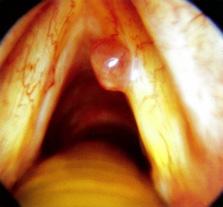

Figura 33. Parálisis de Bell. Nótese que en A) Demuestra incapacidad para levantar la ceja izquierda o generar arrugas en el lado izquierdo de la frente; B) Demuestra dificultad para cerrar el ojo izquierdo e incapacidad para levantar la comisura de la boca izquierda; C) Demuestra caída en la esquina izquierda de la boca, pérdida del pliegue nasolabial izquierdo e incapacidad para cerrar completamente el ojo izquierdo.